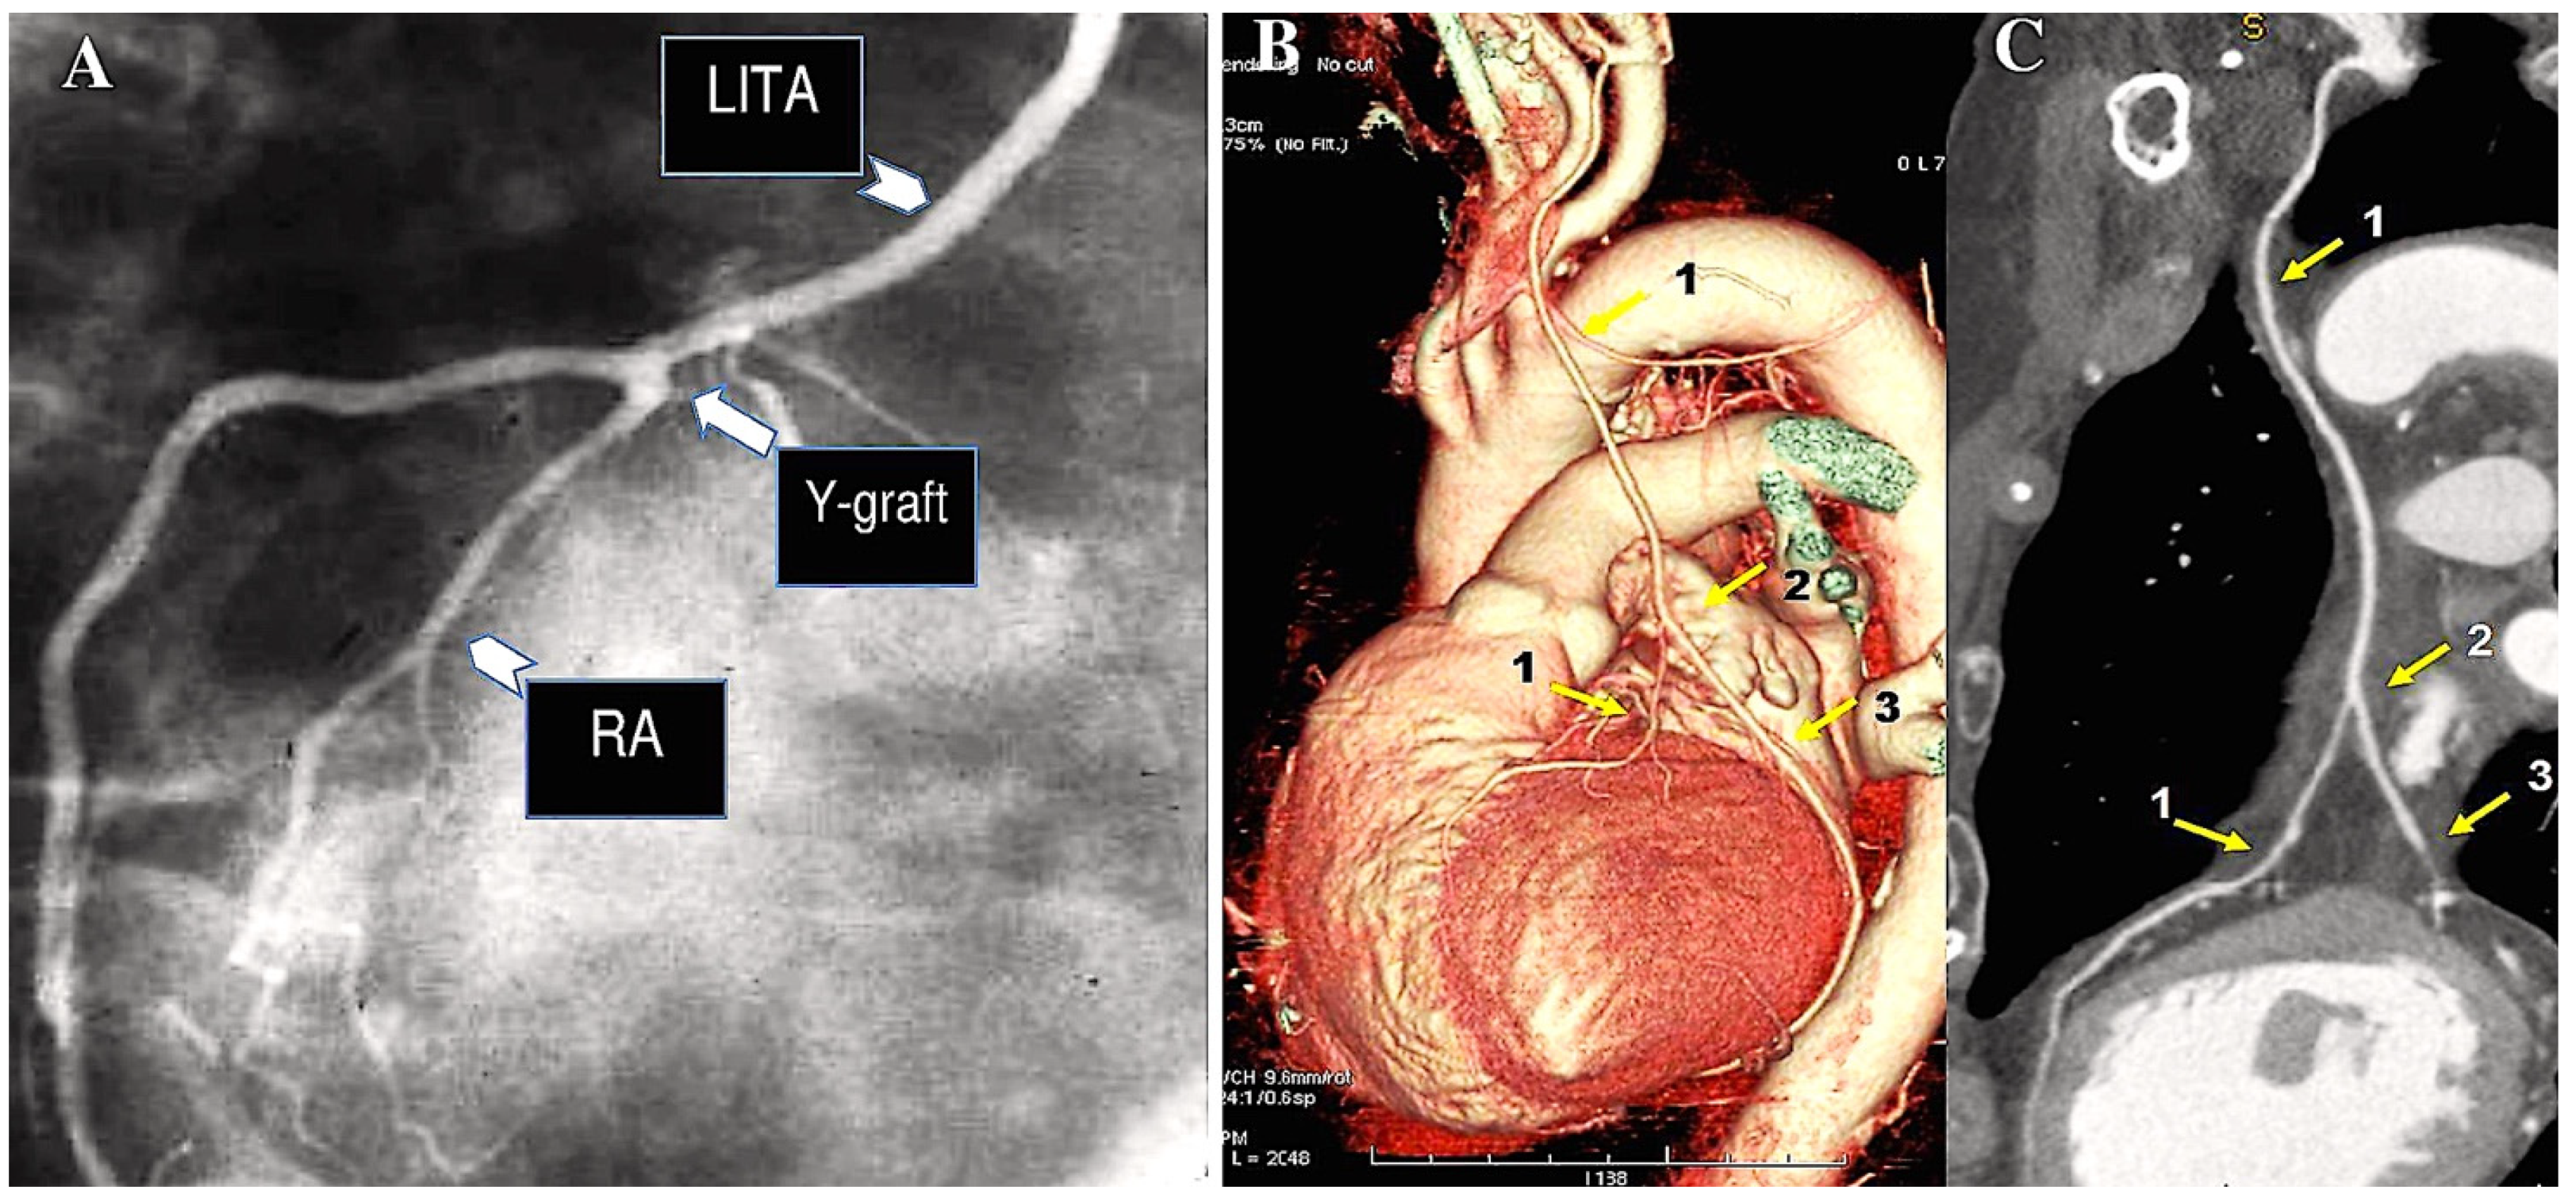

In the case of in situ arterial grafts (such as a left internal thoracic artery graft), the native arterial inflow is retained, thus necessitating an alternative approach (Figure 3).

Figure 3.

The CABG procedure was conducted using arterial conduit (A–C) and including BITA in a Y-shaped configuration (A), the gastroepiploic artery (B), and pedicled LITA-RITA and RA (C). (A): 1. Left internal thoracic artery (LITA); 2. LITA on diagonal branch; 3. LITA on left anterior descending artery (LAD). (B): Gastroepiploic artery on right coronary artery (RCA). (C): 1. Right internal thoracic artery (RITA) on RCA; 2. LITA on LAD; 3. radial artery (RA) on first obtuse branch.

The RA conduit can be employed for sequential revascularisation and sutured as Y-graft to LITA (Figure 4A). Moreover, it is considered to be a prime location for performing proximal anastomosis on an additional RA conduit (Figure 4A). Such conduits may comprise an additional radial artery graft or a free RITA (Figure 4B,C).

Figure 4.

The illustration depicts a CABG procedure utilising bilateral internal thoracic arteries anastomosed with Y-graft technique (A–C). (A): Conventional angiogram demonstrates the patency of the RA. The radial artery is employed as a Y-graft technique (LITA-RA-Y) for sequential anastomoses. (B,C): The Y-graft technique (LITA-RITA-Y) is utilised on the left anterior descending artery (LAD) and on the second marginal branch. 1. LITA-LAD; 2. LITA-RITA-Y; 3. RITA-second marginal branch. Abbreviations: LAD, left anterior descending; LITA, left internal thoracic artery; RA, radial artery; RITA, right internal thoracic artery.